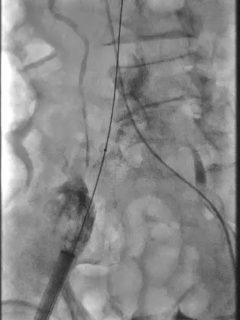

预先置入8mm球囊,准备撤出大鞘

髂外动脉可见造影剂渗出,8mm球囊进行阻断

植入覆膜支架,造影可见轻微出血

植入第二条覆膜支架,无造影剂渗出,手术结束